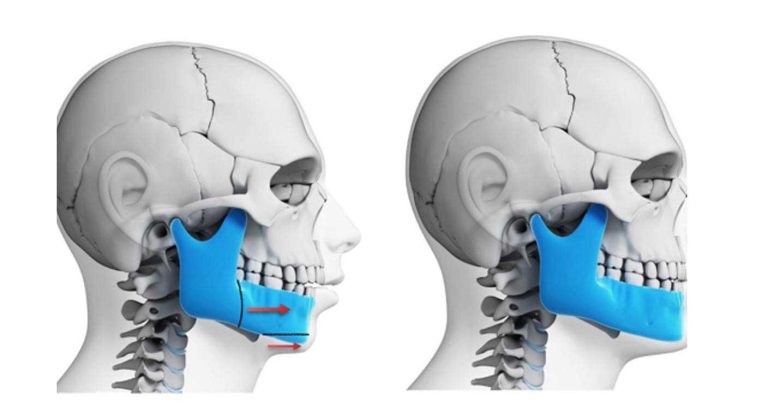

دندان نیش فک بالا، به طور خاص، بیش از هر دندان دیگری مستعد در آمدن دندان بالای لثه یا نهفته شدن است. دلایل متعددی برای این موضوع وجود دارد. اصلی ترین دلیل به زمان بندی و مسیر رویشی پیچیده این دندان مربوط می شود. دندان نیش یکی از آخرین دندان های دائمی است که در قوس دندانی رویش می کند. این رویش معمولا در سنین ۱۱ تا ۱۳ سالگی اتفاق می افتد. در این زمان، بیشتر دندان های دیگر جای خود را در فک گرفته اند. اگر به هر دلیلی، مانند کوچک بودن فک یا بزرگ بودن اندازه دندان ها، کمبود فضا وجود داشته باشد، دندان نیش به عنوان آخرین دندان ورودی، با یک فضای ناکافی مواجه می شود.

علاوه بر این، دندان نیش طولانی ترین مسیر رویشی را در بین تمام دندان ها دارد. جوانه این دندان در ابتدا در بالای فک و نزدیک به کاسه چشم تشکیل می شود. سپس باید یک مسیر طولانی و زاویه دار را به سمت پایین و جلو طی کند تا در جایگاه نهایی خود قرار گیرد. هرگونه مانع یا انحراف در این مسیر طولانی، می تواند باعث گم شدن راه و رویش نابجای آن شود. این موضوع، اهمیت ارتودنسی پیشگیری را نشان می دهد. با ارزیابی های به موقع در سنین پایین تر، می توان مشکلات احتمالی در مسیر رویشی دندان نیش را پیش بینی و از آن ها جلوگیری کرد.

دندان نیش نقش بسیار مهمی در زیبایی لبخند و عملکرد سیستم جونده دارد. ریشه بلند و قوی آن، این دندان را به سنگ بنای قوس دندانی تبدیل کرده است. به همین دلیل، متخصصان ارتودنسی تمام تلاش خود را می کنند تا این دندان ارزشمند را حفظ کرده و به جایگاه صحیح خود هدایت کنند.

- اکسپوژر جراحی و اتصال براکت: پس از ایجاد فضا، جراح لثه یا فک، با یک جراحی کوچک، لثه روی تاج دندان را کنار زده و آن را نمایان می کند. سپس متخصص ارتودنسی یک براکت به آن متصل می کند.

- کشیدن دندان با نیروی ارتودنسی: پس از اتصال براکت، با استفاده از نیروی ملایم و کنترل شده از طریق کش ها یا فنرها، دندان به تدریج به سمت پایین و جایگاه اصلی خود کشیده می شود.

پس از ایجاد فضا، مرحله جراحی فرا می رسد. جراح با یک عمل سرپایی و با بی حسی موضعی، لثه روی تاج دندان را کنار می زند. سپس، متخصص ارتودنسی یک براکت کوچک به سطح نمایان شده دندان می چسباند. در نهایت، مرحله کشش و هدایت دندان آغاز می شود. با استفاده از کش ارتودنسی یا فنرهای مخصوص، نیروی ملایم و مداومی به دندان وارد می شود. این نیرو، دندان را به تدریج و در طی چندین ماه به سمت پایین و جایگاه نهایی خود در قوس دندانی هدایت می کند.